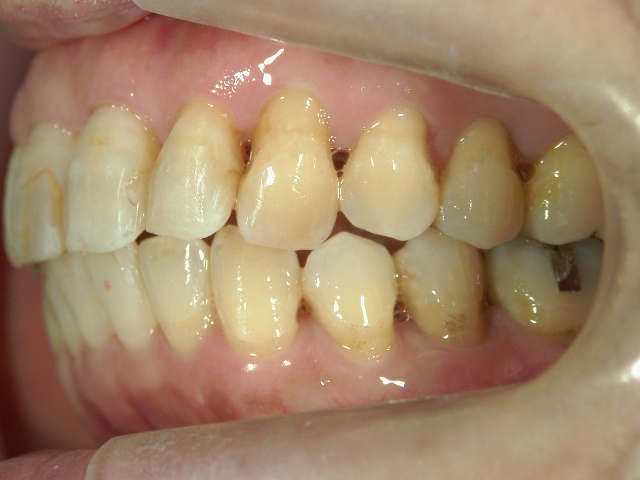

矯正歯科(全顎ワイヤー矯正)治療後

矯正歯科 治療後